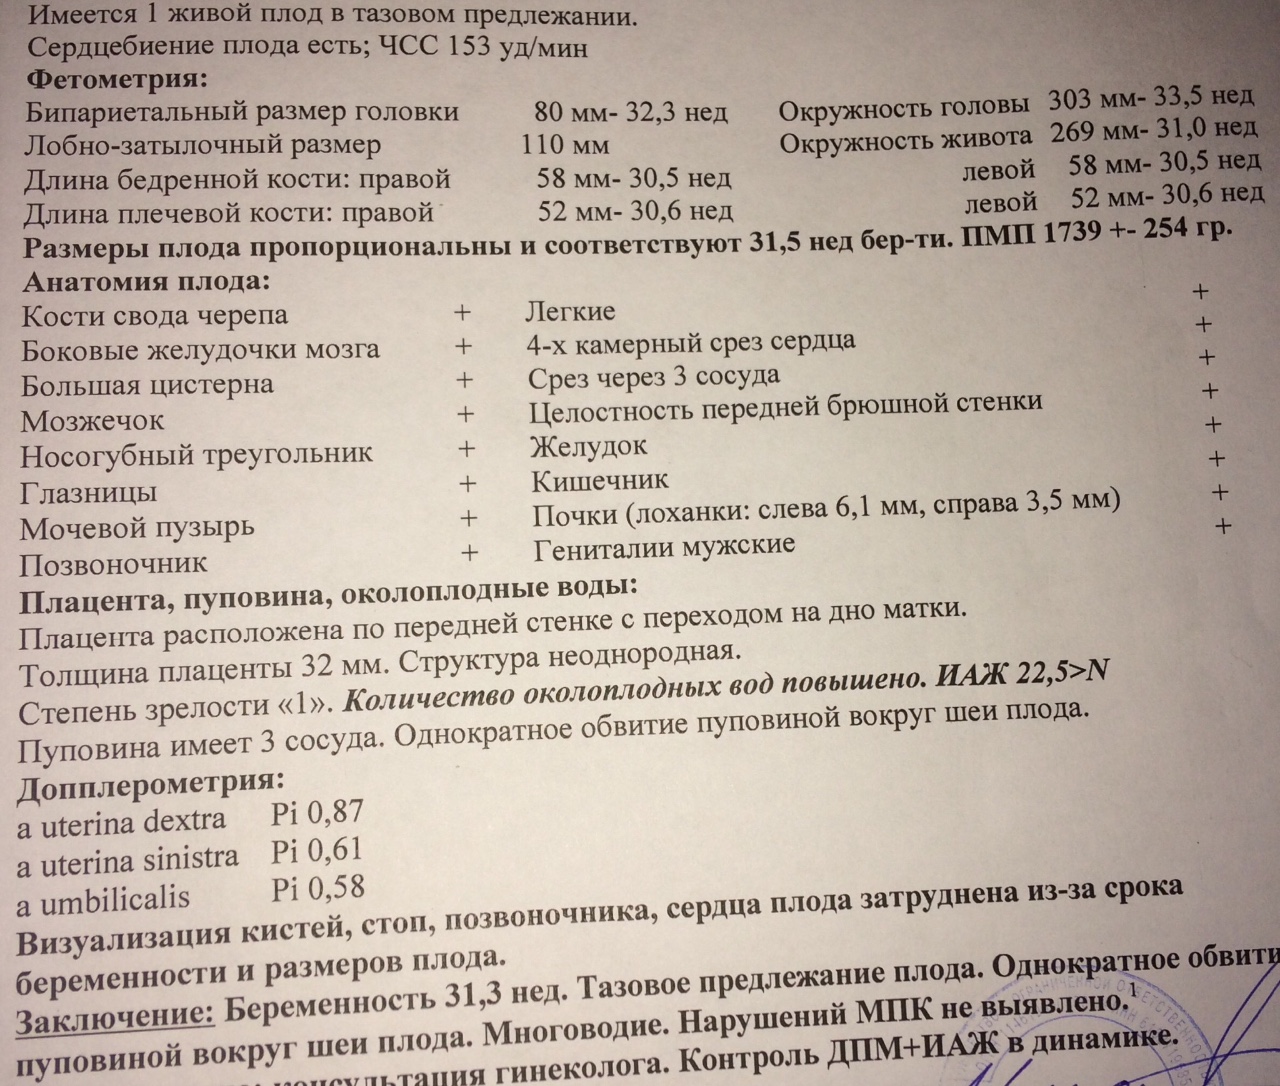

УЗИ на 35 неделе доплер норма

Норма ИАЖ В 35 недель беременности